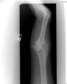

Follow Up

Xrays